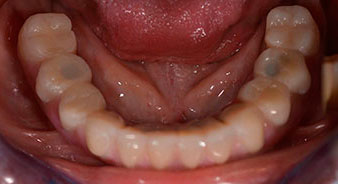

The 64-year-old patient presented with residual dentition of teeth 38, 33 and 43 and a clasp denture in the mandible (Fig. 1 and 2).

Fig. 1

Fig. 2